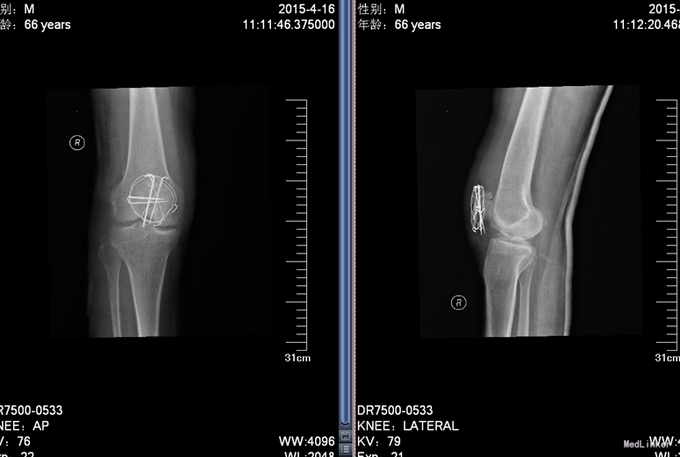

中医诊断:右髌骨骨折(气滞血瘀)西医诊断:右髌骨骨折 治疗:切开复位张力带内固定术。中医辨证论治:根据骨伤科三期辨证理论,早期因瘀血停滞影响骨痂生长,故以活血化瘀,消肿止痛为 主,应用桃红四物汤;中后期补益肝肾,补气养血,应用愈骨胶囊等药物应用。现患者属于骨折早期, 可运用桃红四物汤加减对症治疗,方药如下: 桃仁10g 红花10g 当归12g 川芎12g 赤芍12g 穿山甲6g 柴胡12g 黄芩10g 香附12g 延胡索15g 续断15g 生地12g 甘草6g 3剂 用法:每日一剂,水煎服400ml,分早晚两次温服。 中医调护:避风寒,慎起居,忌生冷,畅情志。

术后复查X线片示骨折复位良好,内固定在位且牢靠。根据骨伤科三期辨证理论,早期因瘀血停滞影响骨 痂生长,故以活血化瘀,消肿止痛为主,应用桃红四物汤。术后证属肝肾亏虚,气血不足,治以补益肝 肾,补气养血,应用愈骨胶囊等药物促进骨折愈合。术后嘱患者继续石膏托外固定,注意陪护,3月内扶 双拐、按指导患肢不负重功能锻炼;休息3个月,加强营养,促进骨折愈合;继续中药应用,促进骨折愈 合;定期复查,(1月、3月、6月);不适随诊。 本病例中医药应用结合手术复位,早期将骨折复位, 中医药早期应用活血化瘀、消肿止痛,可迅速缓解患者症状。中医药中后期应用可促进骨折愈合,加快 术后恢复,可使患者获得满意的术后疗效。